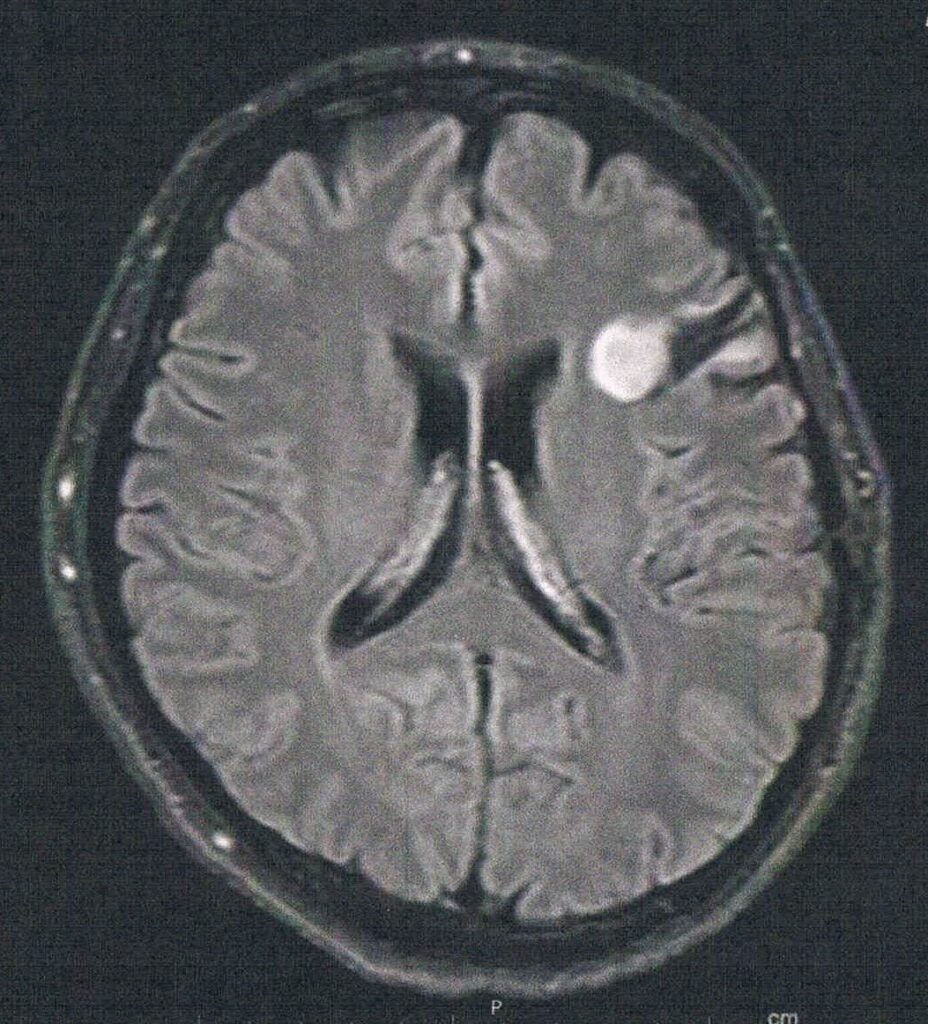

- 造影剤を注射してMRI検査

- 年レベルでおおきくなっている